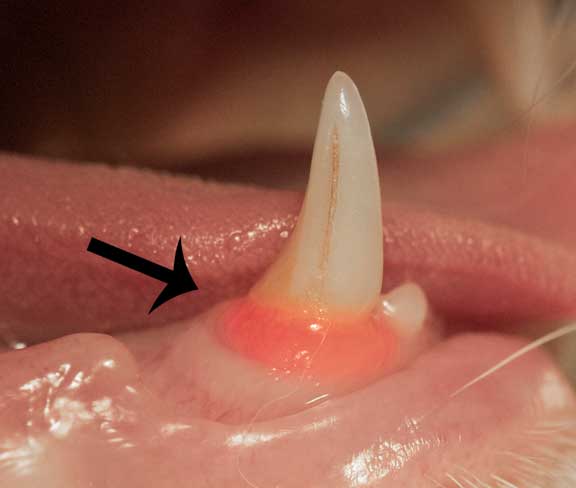

- Dental Disease

Dental Disease is the most overlooked disease in domestic animals. This small mouth of red gum is gingivitis, and can predispose cats to FIP, along with causing problems in organs like the liver, kidneys, and heart.